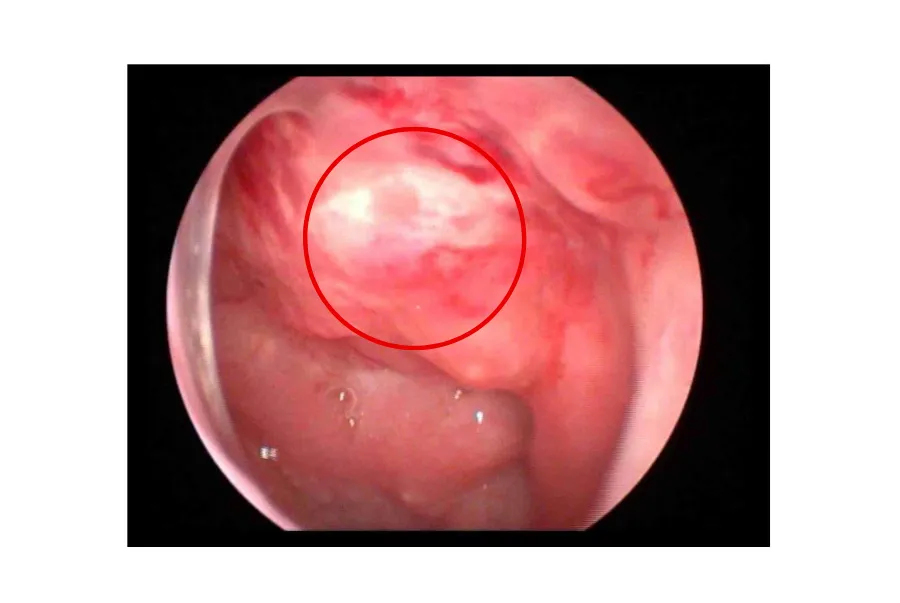

Tại bệnh viện, qua thăm khám lâm sàng và nội soi Tai Mũi Họng, bác sĩ phát hiện một khối u ở vòm mũi họng bên trái cùng bên với tai ù. Hình thái và vị trí khối u có nhiều dấu hiệu bất thường, không giống tổn thương do viêm thông thường, khiến bác sĩ nghi ngờ nhiều đến khả năng tổn thương ác tính vùng vòm mũi họng.

Hình ảnh khối u trong tai trái của cô M

Từ dấu hiệu mờ nhạt này, ThS.BS Đoàn Thị Nguyệt Ánh đã chỉ định sinh thiết khối u để làm xét nghiệm mô bệnh học. Kết quả cho thấy bệnh nhân mắc ung thư biểu mô tế bào vảy kém biệt hóa vùng vòm họng.